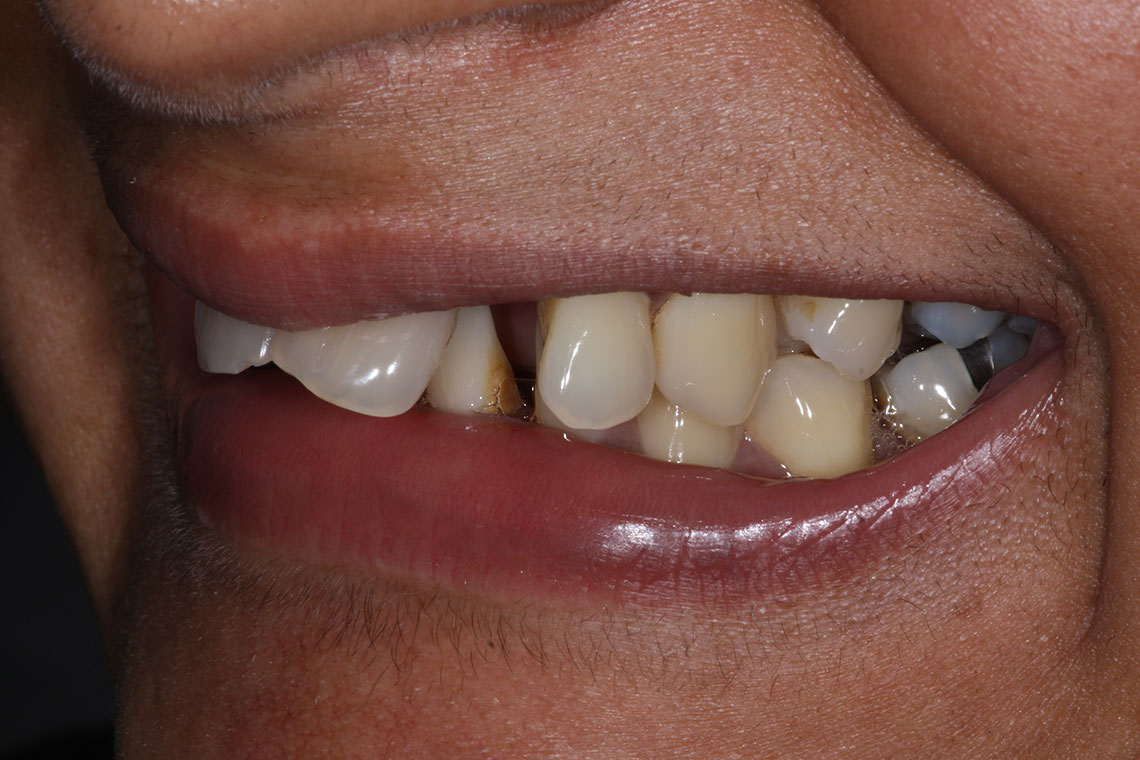

This lovely lady attended with very low confidence due to her teeth and smile. Gum disease and trauma had led to the teeth drifting. One of her front teeth was so loose that it needed to be replaced. We started by providing intensive treatment with our dental hygienist to treat the gum disease. Following this Invisalign® braces were used to align the teeth and the teeth were whitened. A dental implant was then placed to replace the loose front tooth and composite bonding was performed to the adjacent front tooth. The change in the patient’s confidence as a result of this work was breathtaking.